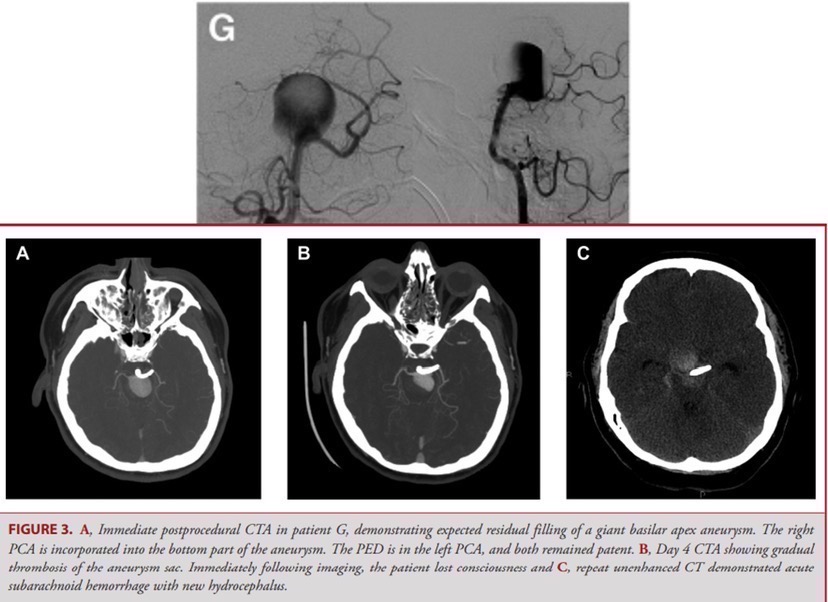

这是一篇迄今最多病例血流导向装置治疗基底动脉尖动脉瘤的多中心回顾性分析文献,随访时间较短(中位数6个月),68.8%的满意闭塞率,死亡1例(6.3%),为术后第四天动脉瘤迟发性出血;2例轻微并发症(12.5%):一例为动脉瘤周围水肿,一例为其他部位颅内出血。令人惊奇的是,这组病例中,竟没有一例发生穿支梗塞(包括无症状性梗塞)!这个结果,给我们带来了不小的信心。

我们特意把这篇文章中死亡病例的影像摘出来做了点分析研判:巨大相对窄颈(最大径25mm)未破裂动脉瘤,一枚pipeline,未填圈,术后即刻可见瘤内部分血栓形成,但血流仍直达瘤颈,最后一张CT平扫也提示出血在瘤顶附近。如果瘤内填圈能否预防出血发生呢?到底填到什么程度才能预防出血?